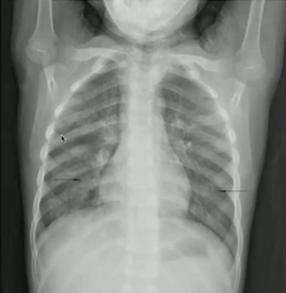

Example3 主诉:足月新生儿高热,胎膜早破。

胸片特点:“马克笔样”弥漫颗粒、团块状阴影;50%伴胸膜积液。

诊断:新生儿肺炎(B组链球菌肺炎):常见于胎膜早破,母亲阴道感染;影像学表现多样,应结合病史及临床表现与TTN、RDS鉴别。

图7.新生儿B组链球菌肺炎

Example4 主诉:过期产儿出生后呼吸困难。

胸片特点:粗条、绳索状阴影(被阻塞的小呼吸道塌陷、不张);过度充气(未阻塞的小气道代偿性过度通气);常见并发症:肺气漏、气胸。

诊断:胎粪吸入综合征(对称性粗条线索状阴影/大片阴影)

图8.胎粪吸入综合征